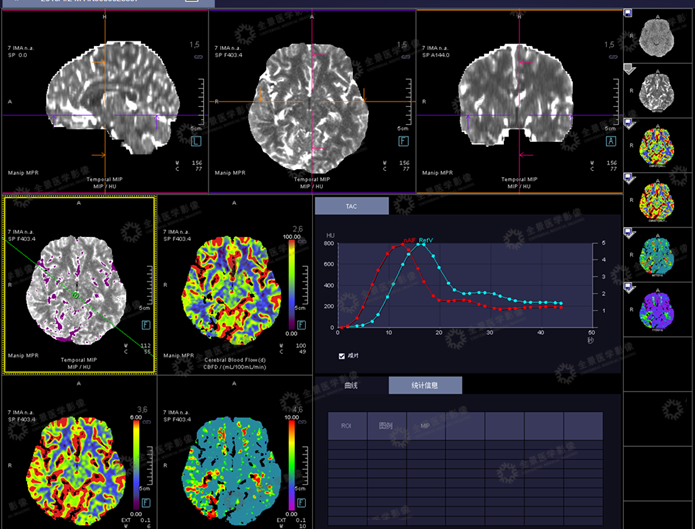

CT灌注成像(CTP)作为功能成像的方法,

临床主要应用于脑卒中缺血的评估。

随着高端CT的自适应4D螺旋扫描模式(摇篮床模式)的引入,探测器限制被克服,从而实现了全脑CT灌注。

头颅灌注示:右枕叶异常灌注,CBF较左侧降低,MTT、TTD时间延长。

右侧额叶、基底节与对侧比较,CBF下降明显,CBV无明显差异,

MTT、TTD时间明显延长。(前循环供血范围)

右侧颞叶与左侧比较,CBF稍增加,CBV无明显差异,MTT、TTD时间稍延长。